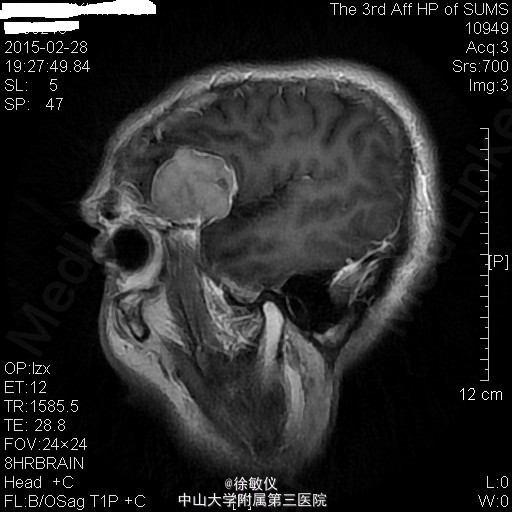

老年男性,主诉:咳嗽、咳痰2月余,头痛、纳差伴四肢乏力5天。 现病史患者2月余前无明显诱因出现咳嗽、咳痰,呈连声咳,咳白色稀薄痰,未予特殊治疗。5天前无明显诱因出现头痛,为右侧颞部持续性隐痛,尚可入睡,伴有纳差,四肢乏力。遂来我院门诊,查胸部CT示:1、左肺上叶尖后段空洞性病变;纵隔多发肿大淋巴结;中~大量心包积液。2、右肺中叶及双肺下叶少许慢性炎症。遂收入院。 查体:生命体征平稳,查体无特殊。 入院后予行心包穿刺抽液,心包积液检查:浆膜腔液总蛋白47.7g/L,乳酸脱氢酶306U/L,浆膜腔积液葡萄糖5.76mmol/L,白细胞计数2150X10E6,颜色黄色,粘蛋白定性试验+/-,红细胞计数1570X10E6,透明度微混,凝固物有凝块,淋巴细胞0.88,中性粒细胞0.12。血清 癌胚抗原>100ug/L。 血清乳酸脱氢酶:358U/L。 暂予头孢美唑钠(悉畅)注射剂2g Q12h,左氧氟沙星氯化钠(可乐必妥)注射液0.6g Qd抗感染治疗。 因患者诉头痛明显,行头颅MR提示:1右侧蝶骨嵴肿物,考虑脑膜瘤;双侧小脑半球及小脑蚓部肿物并双侧小脑半球脑沟脑回样强化,考虑转移瘤并脑膜转移,梗阻性脑积水。 诊断:1、心包积液 恶性肿瘤转移 2、高血压病 2级 高危 3、头部恶性肿瘤 颅内转移 4、脑膜瘤 5、肺部感染 患者肿瘤情况不明,出院后第二天因脑疝死亡。